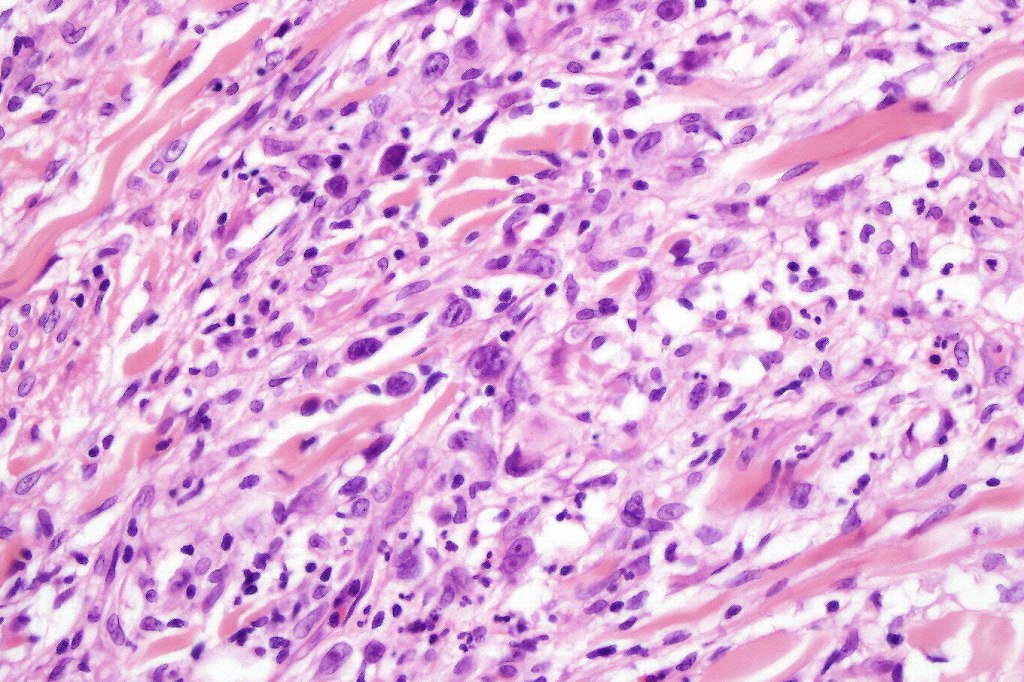

•Type A: 75-80%, wedge shaped infiltrate with base uppermost, large, anaplastic cells with abundant cytoplasm and vesicular nuclei containing prominent nucleoli, can resemble Reed-Sternberg cells, conspicuous mitoses & background infiltrate of lymphocytes, plasma cells, histiocytes, neutrophils & eosinophils